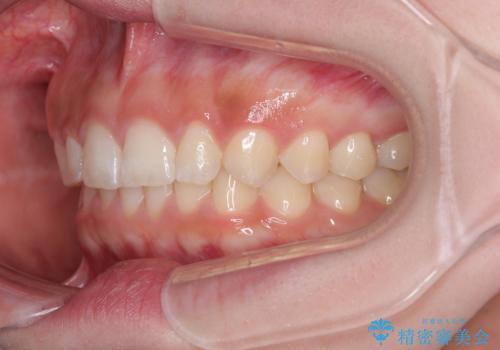

- 前歯のデコボコとディープバイトを気にして来院された患者様です。

左上前歯前方に飛び出しているため、歯列全体が前方に移動している状態でした。

短期間で確実に仕上げたいとのことで、アンカースクリューと補助装置を併用して歯列の後方移動を図り、ワイヤー装置にて矯正治療を行うこととしました。

左上の歯列は補助装置により速やかに移動し、1年程度で奥歯の咬み合わせが改善され、1年3ヶ月の短期間でしっかりと仕上げることができました。